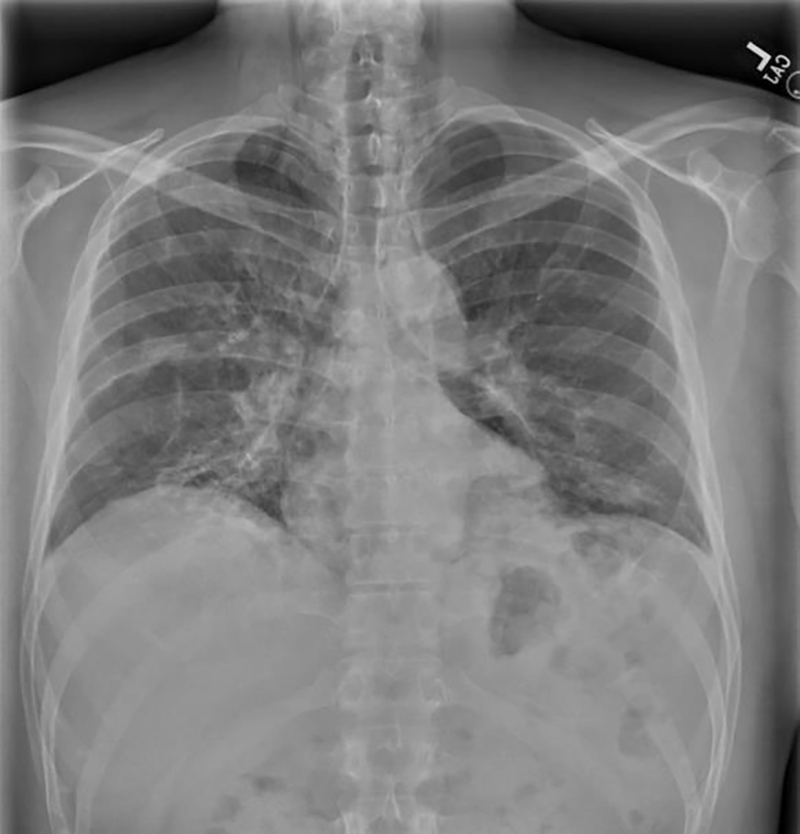

Figure 2

Figure 2. (A) Chest CT shows a large pneumomediastinum with large patchy opacification in the right hilar and posterior lower lobes bilaterally with general fibrotic changes to both lungs. (B) Chest CT at 12 weeks follow-up visit shows less extensive pneumomediastinum.

At a 2-week clinic follow-up, the MDA5 antibody was positive at 91 (<11), and he was diagnosed with anti-MDA5 dermatomyositis. Mycophenolate Mofetil (MMF) 500 mg twice daily was started. At the 6-week follow-up, his muscle power had greatly improved with the resolution of the rashes, and no side effects from MMF were noted. MMF dose was increased to 3 g daily to the target dose. A pulmonary function test was consistent with restrictive lung disease, FEV1 1.89 L (47%), FVC 2.32 (46%), and normal FEV1/FVC ratio. The patient was unable to perform DLCO. At 12-week follow-up, a repeat CT chest demonstrated less extensive pneumomediastinum than the prior exam (Figure 2B).